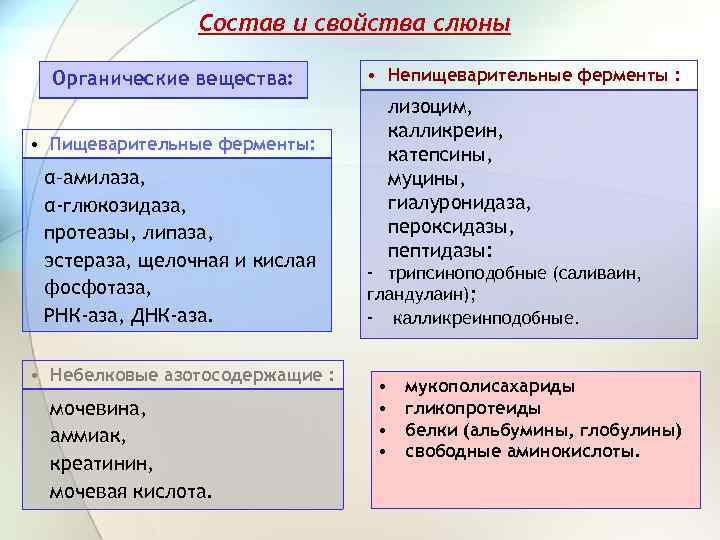

Состав и свойства слюны Органические вещества: • Пищеварительные ферменты: α–амилаза, α-глюкозидаза, протеазы, липаза, эстераза, щелочная и кислая фосфотаза, РНК-аза, ДНК-аза. • Небелковые азотосодержащие : мочевина, аммиак, креатинин, мочевая кислота. • Непищеварительные ферменты : лизоцим, калликреин, катепсины, муцины, гиалуронидаза, пероксидазы, пептидазы: - трипсиноподобные (саливаин, гландулаин); - калликреинподобные. • • мукополисахариды гликопротеиды белки (альбумины, глобулины) свободные аминокислоты.